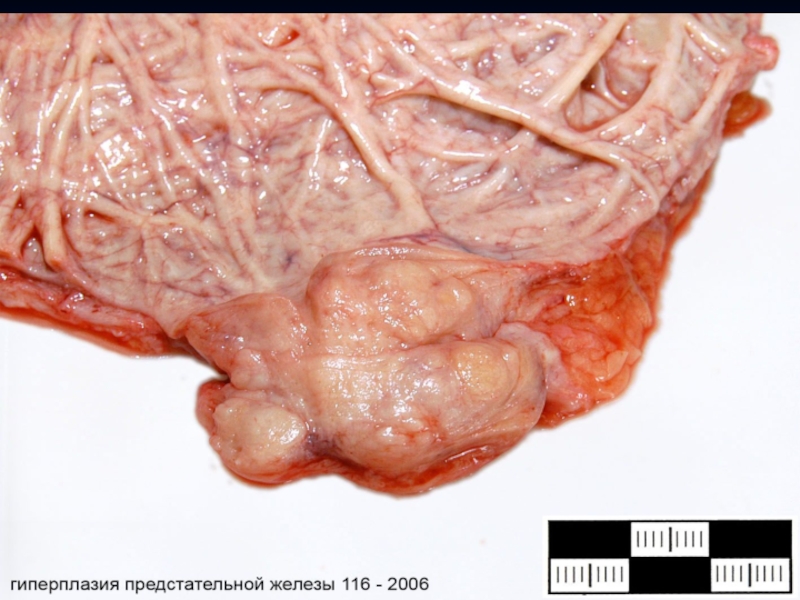

Слайд 6 Аденома – опухоль из эпителия (призматического) железистых органов

и слизистых оболочек. В виде четко отграниченного узла, встречается в

молочной, щитовидной, предстательной, паращитовидной, слюнной, поджелудочной железах, гипофизе, надпочечниках, почках.

На слизистых оболочках выступают над поверхностью в виде полипа (железистый, аденоматозный).